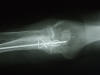

Fractura intertrocantérea de fémur, osteosíntesis